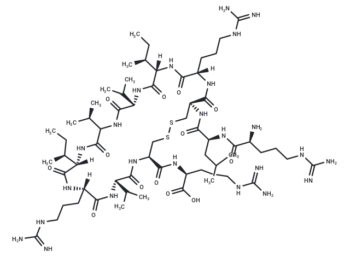

– ANK peptide is a novel peptide designed based on the conserved residue of a single-anchored protein motif. It acts as an inhibitor of γ-synuclein (SNCG) by binding to SNCG, thereby competing with and disrupting the SNCG-BubR1 interaction. This action enhances the sensitivity of breast cancer cells to antimicrotubule agents such as nocodazole and paclitaxel. ANK peptide is useful for tumor research.

Molecular Formula

– C152H244N52O46S2

– 929207-58-9

Molecular Weight

– C152H244N52O46S2

– [C@@H](CC1=CN=CN1)(NC([C@@H](NC([C@@H](NC([C@@H](NC([C@@H](NC(CNC([C@H](CCCCN)N)=O)=O)CC(N)=O)=O)CO)=O)C)=O)CC(C)C)=O)C(N[C@H](C(N[C@H](C(N[C@H](C(N[C@H](C(N[C@@H](CC2=CN=CN2)C(NCC(N[C@@H](CC3=CN=CN3)C(N[C@H](C(NCC(N[C@H](C(N[C@H](C(N[C@H](C(N[C@H](C(N[C@H](C(N[C@H](C(N[C@H](C(N[C@@H](CC4=CC=C(O)C=C4)C(NCC(N[C@H](C(N[C@H](C(N[C@H](C(N[C@H](C(N[C@H](C(N[C@H](C(N[C@H](C(N[C@@H](CC5=CN=CN5)C(NCC(O)=O)=O)=O)CC(N)=O)=O)CCC(N)=O)=O)CCSC)=O)[C@@H](C)O)=O)C(C)C)=O)CC(N)=O)=O)C)=O)=O)=O)CCCNC(=N)N)=O)C(C)C)=O)CC(C)C)=O)[C@@H](C)O)=O)CCC(N)=O)=O)[C@H](CC)C)=O)CS)=O)=O)CC(C)C)=O)=O)=O)=O)CCC(N)=O)=O)CO)=O)C)=O)C(C)C)=O

– Peptide